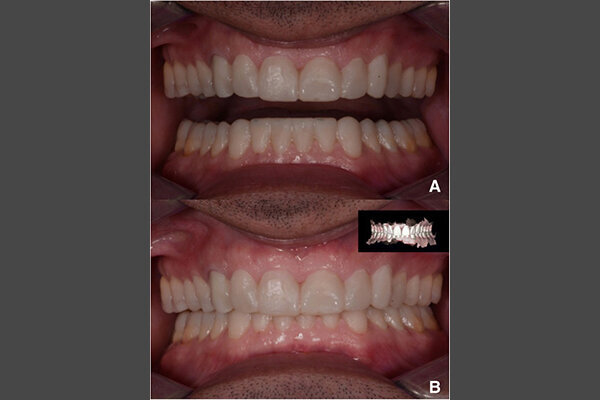

En 2015, un paciente de 47 años se quejó de dolor en la ATM. Teníamos también una solicitud estética, ya que parte de la carilla de uno de los incisivos centrales superiores se había roto (Figs. 1-3). El análisis clínico y radiográfico (Fig. 4) ocasionó una pérdida de altura de la mordida y; una sustancia dental debida a un bruxismo.

Fig. 14. Fotografías intraorales del tratamiento finalizado. a y b Vista frontal. c Vista oclusal de la mandíbula superior. d Vista oclusal de la mandíbula inferior.

Se retiró el exceso de material de fijación, y la oclusión se adaptó y verificó con la tecnología T-Scan (Tekscan). Se usó una férula de resina acrílica removible para proteger las restauraciones finales. Las restauraciones finales se verifican después de seis meses. Las restauraciones estaban estables y no mostraban signos de fractura (Figs. 13-15). El paciente también informó que ya no sufría dolores de cabeza con la nueva altura de la mordida.